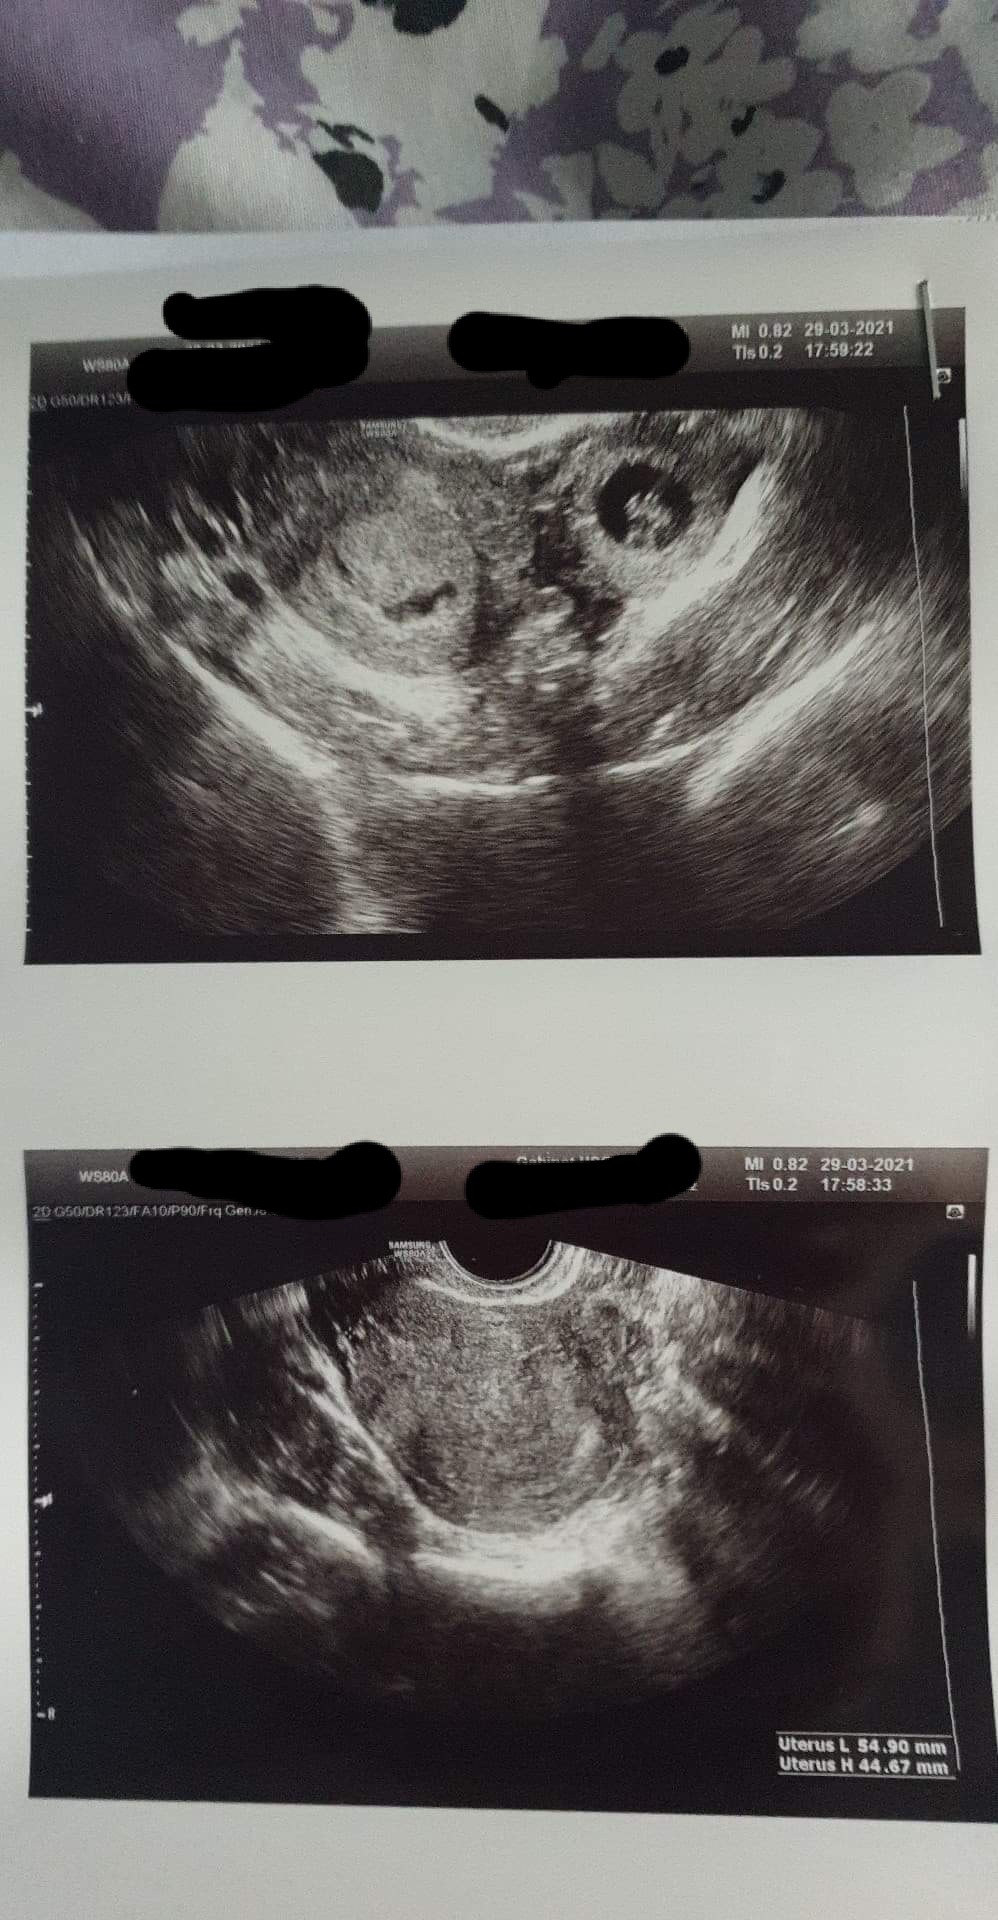

Moja beta w poniedzialek wynosiła ponad 36 tys, czyli byl przyrost.. zrobilam cos co wiele dziewczyn doradzają, poszlam na konsultacje do innego lekarza. I tam doznałam mega szoku, okazalo sie ze nie mam ciazy w macicy, ze nie ma tam pecherzyka który ma 4mm i pokazuje 4 tydz a nie 7, w macicy NIC nie było... a niestety bylo w jajowodzie. Okazało się że jest tam pecherzyk z zarodkiem u którego bije serduszko

.. takze tak to wszystko wygląda, radze koniecznie konsultować z innymi lekarzami, moj bardzo sie pomylił i wedlug ustaleń mialam przyjsc w czwartek na usg jak hcg rosło. Kto wie czy gdybym czekala na czwartek czy w tym czasie nie pekl by mi jajowod.. dołączam kilka zdjęć.. ostatnie zdjęcie jest od 1 gina który widzial q macicy pecherzyk 4mm i krwiaka, pozdrawiam!!